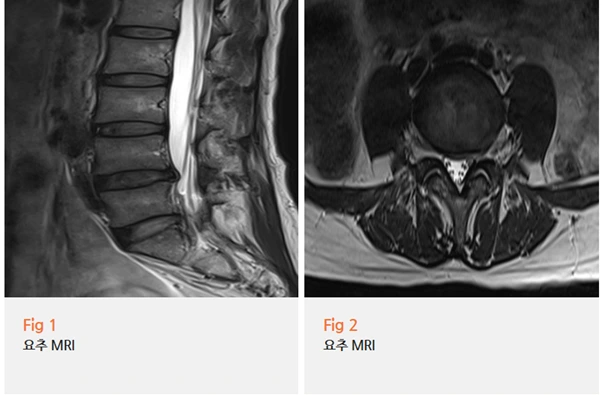

요추 MRI와 고관절 MRI를 당일 함께 시행했어요.

환자분께서는 고관절이 더 아픈데 왜 허리도 찍어야 하냐고 살짝 의아해하셨지만,

검사 결과를 보시고 나서 그 이유를 바로 이해하셨어요.

요추 추간판 탈출증 소견이 명확하게 확인됐고,

하지 근전도 검사에서는 만성 요추 신경근병증 소견도 함께 나왔어요.

반면 고관절 자체에는 뚜렷한 구조적 이상이 없었습니다.

즉, 고관절 통증과 다리 저림의 진짜 원인은 허리에서 내려오는 신경 압박이었던 거예요.